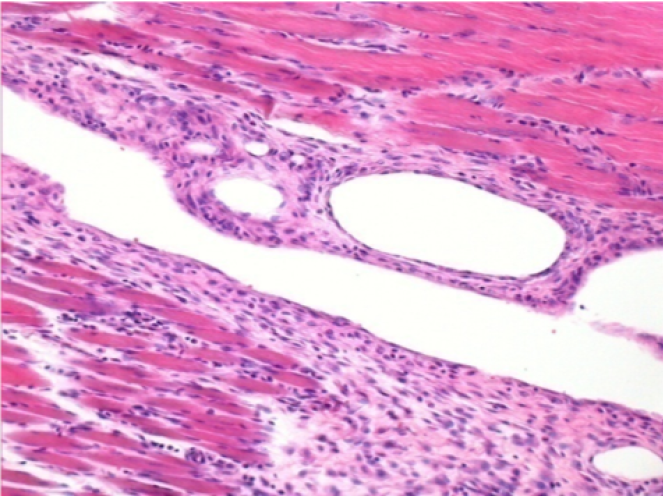

بعد شهر من حقن إندوبيل

بعد شهر واحد من حقن Endopeel 0.1 مل في العضلة أمام الظنبوب اليمنى.

ما يظهر باللون الأسود في الصور ليس نخرًا كما يتصور بعض العلماء!

في الواقع ، يجب أخذ 4 استنتاجات في الاعتبار :

- قطعة أثرية من التلوين

- عدم وجود نخر

- عملية بيولوجية

- موت الخلايا المبرمج

L : Control-100xD30

R:100xD30

R :400xD30